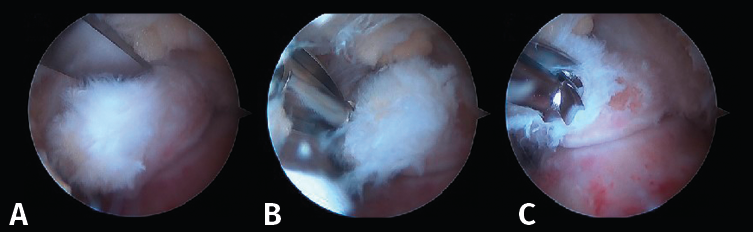

Tras la disección completa del PPA y la evaluación y el tratamiento de la patología asociada del FHL, si es necesario, podemos iniciar el procedimiento de resección ósea(11,12,13). Así, en caso de pinzamiento óseo, los procedimientos se realizan de acuerdo con la etiología de este (Figuras 8 A, B y C).

Figura 8. A: en una primera opción, se realiza la resección ósea mediante un osteotomo de 5 mm; B y C: la segunda opción es realizar la resección mediante el uso de una fresa artroscópica.

En ocasiones, está desprendido y se puede retirar fácilmente con una pinza grasper. Pero, si está fijado por fibrosis, es posible separarlo mediante el empleo de un desperiostizador o el sinoviotomo. Pero, cuando la fusión está calcificada, será preciso emplear un osteotomo de 5 mm introducido por el portal artroscópico. El fragmento escindido se extrae mediante una pinza grasper. También se puede utilizar un terminal de fresado para hacer la resección o para finalizarla regularizando los bordes del hueso. El límite del cartílago de la articulación subastragalina constituye el mejor punto de referencia para asegurarnos una resección adecuada (Figura 9).

Proceso posterolateral del astrágalo hipertrófico o proceso de Stieda

En los casos de PPAH, el hueso se puede cortar mediante el empleo de un osteotomo de 5 mm introducido por el portal artroscópico o resecarse mediante un terminal motorizado de fresa artroscópica. El uso del osteotomo no es fácil debido a que el ángulo del corte no es perpendicular; por ello, la mayoría de las veces es necesario finalizar la resección ósea mediante la fresa de artroscopia.